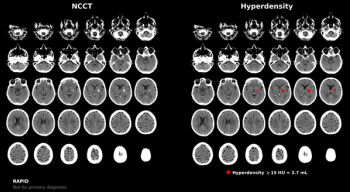

RapidAI’s Rapid Hyperdensity tool reportedly allows quicker assessment of hyperdense tissue in the brain via non-contrast computed tomography (CT) scans.